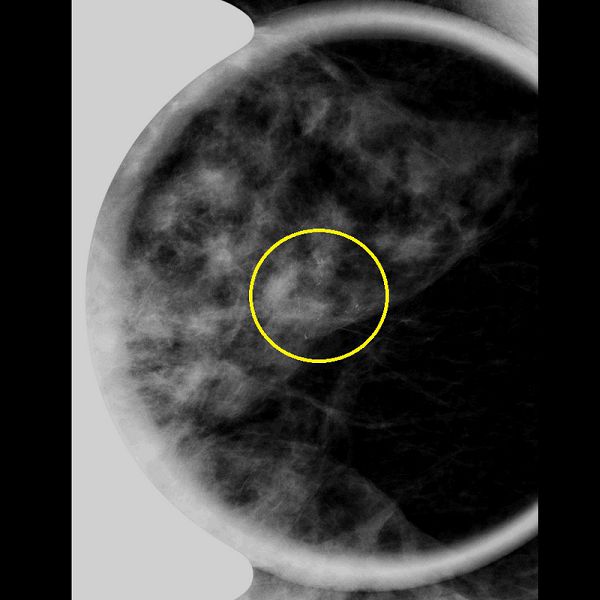

63歲的林女士一向身體健康,日前看到住家附近的乳癌篩檢巡迴車,心血來潮下便上車檢查,沒想到卻收到要到醫院進行複檢的通知。她來到台北慈濟醫院乳房外科張健輝醫師的門診進一步切片檢查,右側乳房確診為乳癌原位癌。為了能夠不影響生活,早日回到工作崗位,在醫師的建議下林女士接受「經腋下乳頭保留乳房全切除手術」,並在手術中直接由整形外科醫師重建乳房。由於是微創手術,林女士恢復得相當好,隔天就可以自由活動,術後兩天出院,回歸正常生活,按時追蹤。

乳癌常年高居台灣女性好發癌症之首,好發於四五十歲的中年女性,但隨著飲食和生活習慣西化,發生年齡層日益下降,而隨著早期診斷的普及,越來越多患者在「原位癌」的階段被診斷。台灣統計,乳癌患者中,約有四分之一為原位癌,張健輝醫師說明:「原位癌因為尚在乳管內,未侵犯乳管外組織,所以術後只需口服荷爾蒙藥物即可,許多人也因此低估危險性。雖然原位癌惡性度相對其他乳癌較低,但仍是乳癌進展的開始,必須謹慎面對、儘早處理。」

即使尚未擴散,原位癌的標準治療仍是手術切除。目前的手術方式有乳房部分切除與乳房全部切除兩種,部分切除在術後須搭配每日放射線治療共25至30次,且無法確定其他部位是否有正在進展的癌症,必須密切追蹤。乳房全部切除則有傳統連同皮膚、乳頭一起切除的方式跟新式保留乳頭的微創全切除手術,後者是醫師在病人腋下開一個約4公分左右的傷口,伸入手術器械後,將乳腺與皮瓣、胸大肌分割開來,再將乳腺從微創切口抽出。病人若選擇在一次手術中同時重建乳房,整形外科醫師即在此時將矽膠由微創切口置入重建。張健輝提到,此類術式有可能因為血流供應不佳導致乳房重建後表皮缺血壞死,但隨著技術進步,表皮壞死的機率已經大幅下降;此外,許多用傳統手術切除整個乳房的病人在術後會因為外觀改變造成心理創傷,國外研究發現,傳統手術後且未重建以前,有50%的病人有至少一個精神科診斷,其中50%是焦慮症,27%是憂鬱症;而新式的微創手術保留了原始皮膚跟乳頭,術後外觀與原本的樣子幾乎無異,也降低病人術後的心理壓力。